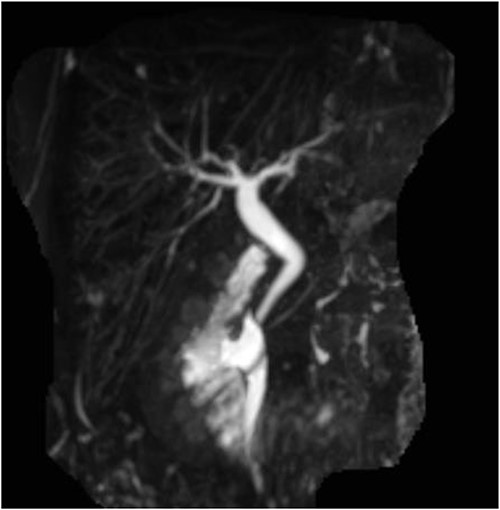

The patient was discharged home on recovery and planned for outpatient MRCP and repeat LFTs. MRCP showed no gallbladder or cystic duct identified consistent with congenital agenesis (Figs 3 and 4). CBD was mildly dilated to 9 mm but tapers appropriately to the ampulla with no evidence of biliary stricture or choledocholithiasis. The repeat LFTs were normal.

Post-operative MRCP confirming congenital gallbladder agenesis.